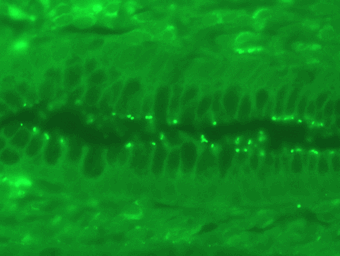

Z-Stackimage; Stomach lining, Total bacteria FITC, probably Helicobacter pylori.

Courtesy of the Medizinische Hochschule Hannover, Germany.

Some examples of FISH images

The detection of whole-bacterial cells via the labelling of specific nucleic acids with fluorescently labelled oligonucleotide probes is called fluorescence in situ hybridization (FISH)